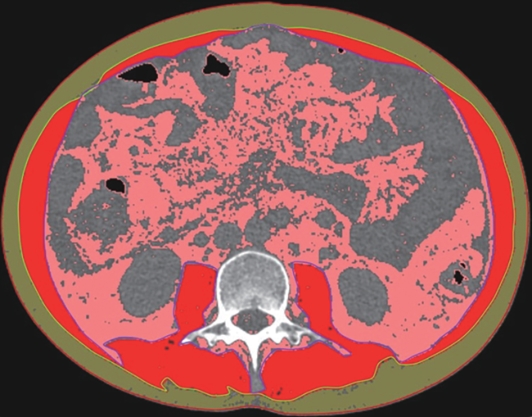

Value of internal stratification analysis of abdominal wall muscles in predicting complications after orthotopic liver transplantation

Xin SHI, Chongxiao LIANG, Bei ZHANG, Jiping WANG

2025, 41(2): 314-321. DOI: 10.12449/JCH250218

Abstract(759) HTML (355) PDF (3265KB)(57)

Abstract:

Objective  To divide the muscle into different subzones according to different density ranges using the stratified analysis on the basis of myosteatosis, and to investigate the effect of muscle density changes on complications (Clavien-Dindo grade ≥Ⅲ) after orthotopic liver transplantation (OLT).  Methods  A retrospective analysis was performed for the medical records of 145 patients who underwent OLT in The First Hospital of Jilin University from May 2013 to September 2020, and with the plain CT scan images of the largest level of lumbar 3 vertebrae of each patient as the original data, Neusoft Fatanalysis software was used to measure related muscle parameters. The independent-samples t test was used for comparison of normally distributed continuous data between two groups, and the Mann-Whitney U test was used for comparison of non-normally distributed continuous data between two groups. The chi-square test or Fisher test was for comparison of categorical data between two groups. RIAS software was used to extract clinical features and perform analysis and modeling, and three machine learning models of logistic regression (LR), support vector machine (SVM), and random forest (RFC) were constructed. The receiver operating characteristic (ROC) curve, the calibration curve, and the decision curve were plotted for each model to calculate the area under the ROC curve (AUC), sensitivity, specificity, precision, F1 score, and accuracy.  Results  The three machine learning models of LR-C, SVM-C, and RFC-C were established based on the 7 clinical features before muscle stratification analysis, among which the RFC-C model had an AUC of 0.803, a sensitivity of 0.588, and a specificity of 0.778 in the test set. Among the models of LR-CS, SVM-CS, and RFC-CS established based on the 16 clinical features after muscle stratification analysis, the LR-CS and SVM-CS models had an AUC of 0.852 in the test set, with a sensitivity of 0.765 and 0.706, respectively, and a specificity of 0.889 and 0.926, respectively. Comparison of the AUC, sensitivity, specificity, precision, F1 score, and accuracy of each model in the test set before and after muscle stratification analysis showed that there were improvements in the parameters of the predictive model after muscle stratification analysis. Comparison of the decision curves and calibration curves of each predictive model showed that the LR-CS and SVM-CS models had good efficacy in predicting postoperative complications (Clavien-Dindo grade≥Ⅲ) in OLT patients.  Conclusion  On the basis of myosteatosis, the division of the muscle into different subzones according to different densities using the stratified analysis has a certain value in predicting postoperative complications in patients with OLT.